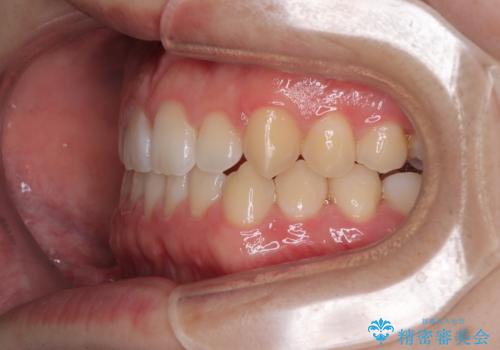

- 「前歯のすきっ歯が気になる」「食べ物が歯の間に詰まりやすい」とのお悩みで来院された20代男性の患者様です。

歯と歯の間に隙間がある**空隙歯列(すきっ歯)**は、見た目の問題だけでなく、食片圧入による歯肉の腫れや、隣接面う蝕のリスク増加につながることがあります。

診査により舌突出癖が認められました。この癖は、すきっ歯の原因となるだけでなく、矯正後の後戻りリスクを高めます。